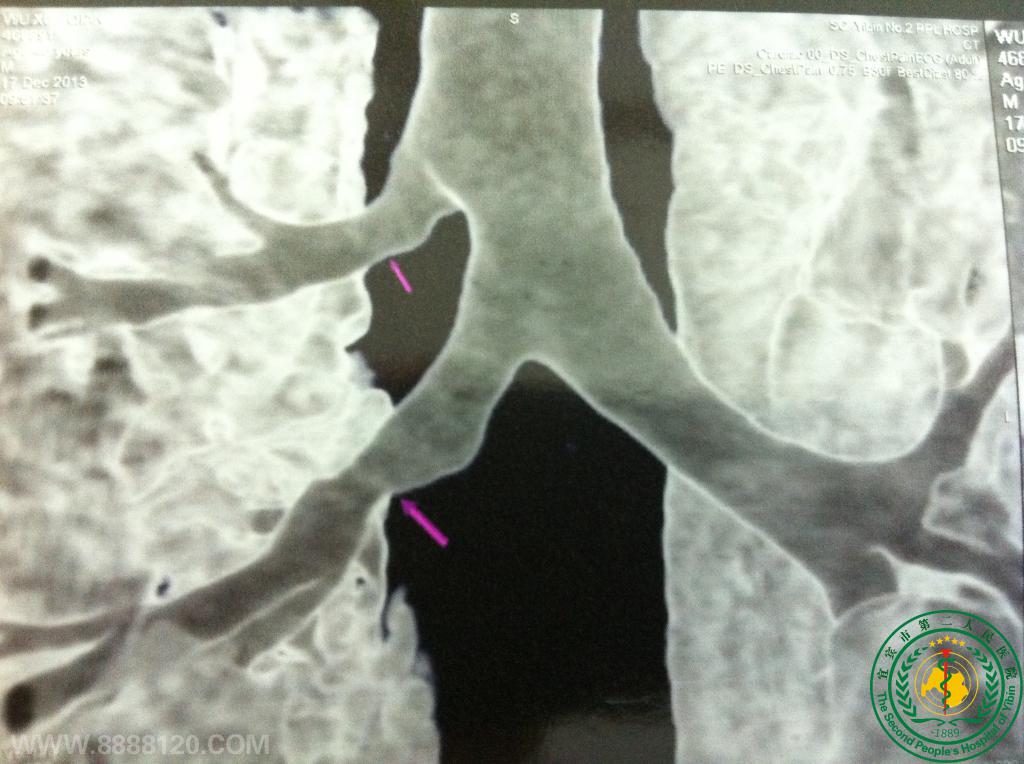

宜宾市第二人民医院胸心外科成功救治一名右肺上下叶支气管完全断裂重伤员(右上叶支气管发育异常)

2013年11月22日凌晨3点宜宾市第二人民医院胸心外科收治了一位来自川南某煤矿的重伤员,该吴姓伤员是在井下被矿车挤压受伤的,入院时呼吸极度困难、病情十分危重,急诊胸部CT检查提示:右侧气胸,右肺压缩90%,右侧多发肋骨骨折,广泛纵隔和皮下气肿。紧急给以吸氧和右侧胸腔闭式引流等抢救治疗,病情仍危重,氧饱和度低,立即给予气管插管呼吸机辅助呼吸,氧饱和度维持在80-90%,右胸腔引流出大量气体,复查CT示,右肺仍未复张,考虑支气管损伤可能,立即进行紧急手术前准备,完善术前沟通谈话和相关签字手续,于上午10时许入手术室进行剖胸探查术,术中探查发现右肺完全不张,右肺下叶支气管完全横行断裂、在奇静脉平面见右肺上叶支气管完全横行断裂,肺血管无损伤,术中用两个手指分别堵塞右肺上下叶支气管近断端,嘱麻醉师鼓肺,待氧饱和度升至95%以上时,先用3-0 porlin缝线连续缝合作右上叶支气管吻合,手术中采用手术台上右肺下叶远端支气管插管用另外一台呼吸机间断通气的方法维持血氧饱和度,待右上叶支气管吻合完毕后,同法用3-0 porlin缝线连续缝合作右下叶支气管吻合,手术中得到了麻醉科医师的密切配合,手术过程紧张有序,顺利完成手术,术毕嘱麻醉师鼓肺,右肺上下叶复张良好,支气管断端无漏气,血氧饱和度升至100%,术后病人生命体征平稳,恢复顺利,已于近期痊愈出眼院。

手术前闭式引流术后        箭头示支气管吻合处,显示                                             手术后胸片显示肺复张良好

仍然肺不张                右肺上叶支气管发育畸形